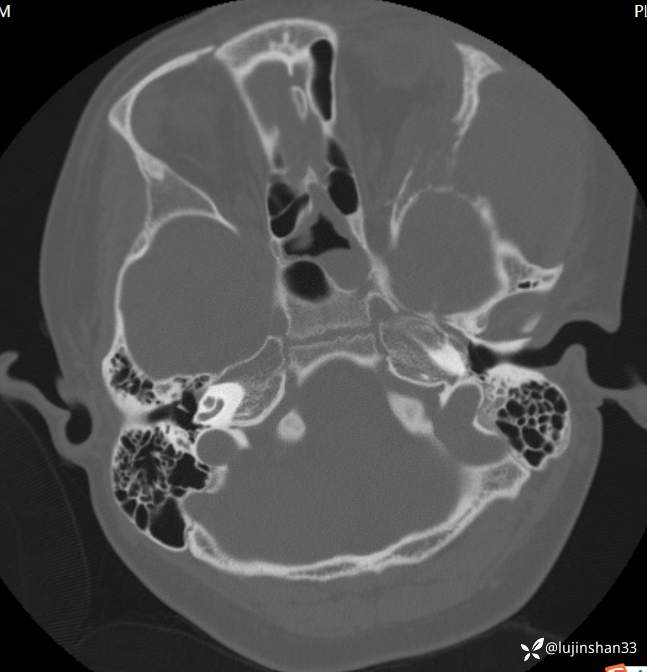

颞骨CT:2020年12月